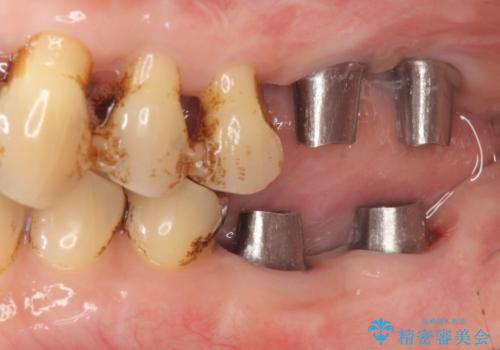

再生治療、歯周外科を行うことで歯周病治療を行い、残すことのできる歯の歯周環境を整える。

残すことのできない歯は抜去したのち骨造成を含めたインプラント治療を行い、しっかりとした咬合関係を確立していきます。

治療期間はかかりましたが、しっかりと歯周病治療・インプラント治療を行ったおかげで歯周病の状態は非常に良くなり、安定した咬合関係を確立することができました。